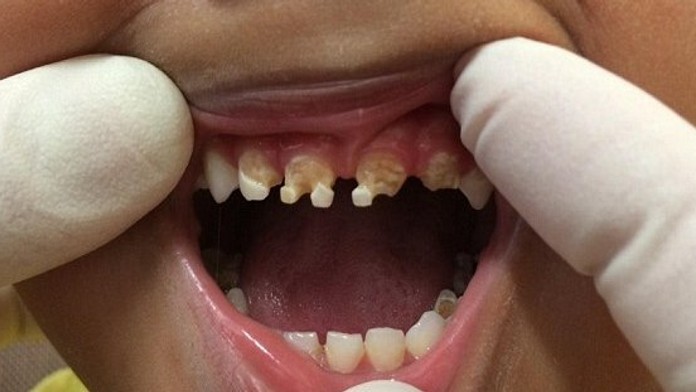

Znepokojujúce fotky detských zubov. Toto spôsobujú sladené nápoje

Vek, kedy sa deťom začínajú kaziť zuby sa stále znižuje. To, že dentisti plombujú mliečne zuby, už nie je žiadna rarita. Keď ale 18-mesačné dieťa príde o celý mliečny chrup, to už je viac než alarmujúce. Rodičia podceňujú výber nápojov, ktorý deťom ponúkajú. Aj keď majú ratolesti najradšej sladké džúsy a malinovky, mamičky by ich chúťky mali ignorovať. Ak ste vy tak doteraz neurobili, pozrite sa, čo všetko spôsobujú sladené nápoje.

Ak ratolesti, ktoré obľubujú sladené nápoje, nemajú ani vzťah k umývaniu si zubov, potom je to čistá pohroma a so zdravým mliečnym chrupom sa môžu rozlúčiť. Zubár odporúča rodičom, aby deťom obmedzili príjem cukru najmä medzi hlavnými jedlami.

Denník DailyMail zverejnil šokujúce snímky malých detí, ktoré si zničili chrup skôr, než im poriadne narástol. Fotky im poskytli austrálski dentisti, ktorí tak nad nedôslednými rodičmi zdvíhajú varovný prst.